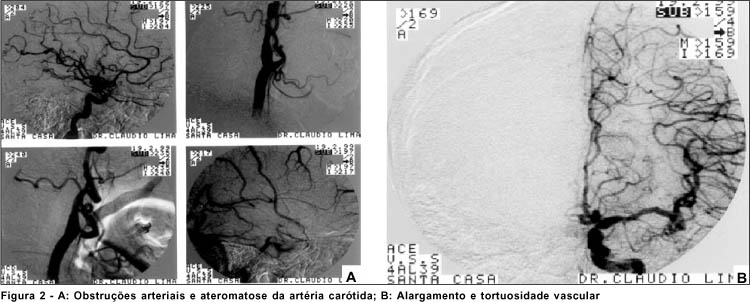

Em 17/9/98, W.M., masculino, 51 anos, diabético e hipertenso apresentava perda de visão bilateral há 5 horas. O exame inicial apresentava ausência de percepção luminosa bilateral, nenhuma alteração à biomicroscopia, pressão intra-ocular normal e reflexos pupilares normais. A fundoscopia apresentou atenuação arteriolar, presença de hemorragias discretas em chama de vela e poucos exsudatos algodonosos em pólo posterior - retinopatia esclero-hipertensiva. A tomografia computadorizada do crânio revelou área de infarto isquêmico cerebral em ambos hemisférios (Figura 1). A avaliação cardiológica através do exame clínico e do ecocardiograma revelou miocardiopatia segmentar do ventrículo esquerdo, déficit sistólico global importante, insuficiência mitral e tricúspide discreta e grande trombo apical no ventrículo esquerdo. O paciente foi acompanhado durante 8 meses e não apresentou melhora da acuidade visual.

No caso 1, a presença de um êmbolo de origem cardíaca pode ter tido importância no aparecimento do evento isquêmico cerebral. A embolização é uma causa freqüente de obstrução da circulação retiniana e êmbolos cardíacos ou carotídeos são os mais comuns(7-8). A oftalmoscopia binocular indireta não mostrou sinais que justificassem a ausência de percepção luminosa bilateral. O campo visual neste caso foi inviável pela ausência de percepção de luz. A tomografia computadorizada de crânio (Figura 1) auxiliou o diagnóstico ao revelar área de infarto isquêmico cerebral em ambos os hemisférios. A alteração fundoscópica no segundo caso (oclusão venosa da arcada temporal em olho direito) poderia dificultar o diagnóstico, entretanto foi detectada somente no olho direito enquanto que a perda visual foi bilateral. Tais achados fundoscópicos poderiam, provavelmente, ter surgido antes da cegueira cortical ou concomitantes, uma vez que tanto a oclusão venosa da retina quanto a cegueira cortical bilateral possuem como principais fatores de risco hipertensão arterial sistêmica e doenças cardiovasculares(7). A tomografia computadorizada de crânio revelou infartos seqüelares occipitais bilaterais e ateromatose bicarotideana. Neste caso também havia alterações vasculares e isquêmicas à arteriografia (Figuras 2A e B). Em ambos os casos os pacientes apresentaram diminuição da acuidade visual, reflexos pupilares praticamente normais e ausência de alterações na oftalmoscopia binocular indireta. Tal quadro e os achados tomográficos caracterizaram o diagnóstico(9). O acompanhamento subseqüente dos pacientes foi realizado simultaneamente por neurologista, cardiologista e oftalmologista. O primeiro caso foi acompanhado pelo oftalmologista por 8 meses e, atualmente, faz controle ambulatorial. Não ocorreu melhora da acuidade visual em nenhum dos olhos. O segundo paciente foi submetido, no Departamento de Retina, a fotocoagulação da oclusão de ramo venoso em olho direito e encontra-se em controle ambulatorial. Apresentou melhora da acuidade visual para percepção luminosa no olho direito e manteve percepção luminosa no olho esquerdo, depois de 1 ano de seguimento. De acordo com a literatura médica, o prognóstico da cegueira cortical é reservado, mas em alguns casos pode haver o retorno gradual da visão até percepção luminosa e de movimentos de mãos (9). Normalmente o prognóstico depende de causa, gravidade, duração da doença e melhoria inicial rápida do quadro(5). Aldrich e colaboradores em 1987 observaram que em 15 pacientes com cegueira cortical o melhor prognóstico foi observado naqueles com menos de 40 anos, sem fatores de risco, como hipertensão arterial sistêmica e diabetes mellitus, e sem alterações cognitivas, de linguagem ou de memória(9). Nos presentes casos, a acuidade visual não melhorou, a não ser no segundo caso, no qual ocorreu leve melhora da percepção luminosa em olho direito. Levando em conta que ambos tinham mais de 40 anos de idade, hipertensão arterial e um deles também diabetes mellitus, pode-se dizer que a evolução e o quadro clínico de ambos estão de acordo com os dados observados na literatura(10). Cuellar & Sanchez também relataram uma melhora da acuidade visual em poucos dias de evolução, em pacientes jovens com cegueira cortical pós-operatória(11).